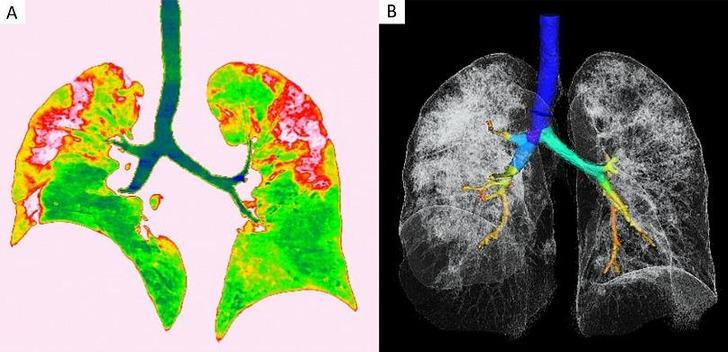

Covid-19'dan kaynaklı zatürre hastası 54 yaşındaki bir kadının transversal ve koronal bilgisayarlı tomografi (BT) görüntülerinde pulmoner lezyonların üst lobda daha yaygın olduğu görülüyor.

Vuhan kentinden döndükten sonra bir hafta boyunca ateşi 38.5 dereceden düşmeyen kadına, nefes darlığı, öksürük ve halsizlik semptomlarıyla hastane yattıktan sonra Covid-19 testi yapıldı. Test sonuçları pozitif çıkan hastaya zatürre teşhisi kondu. Uygulanan tedaviyle söz konusu hastanın semptomlarının hafiflediği rapor edildi.